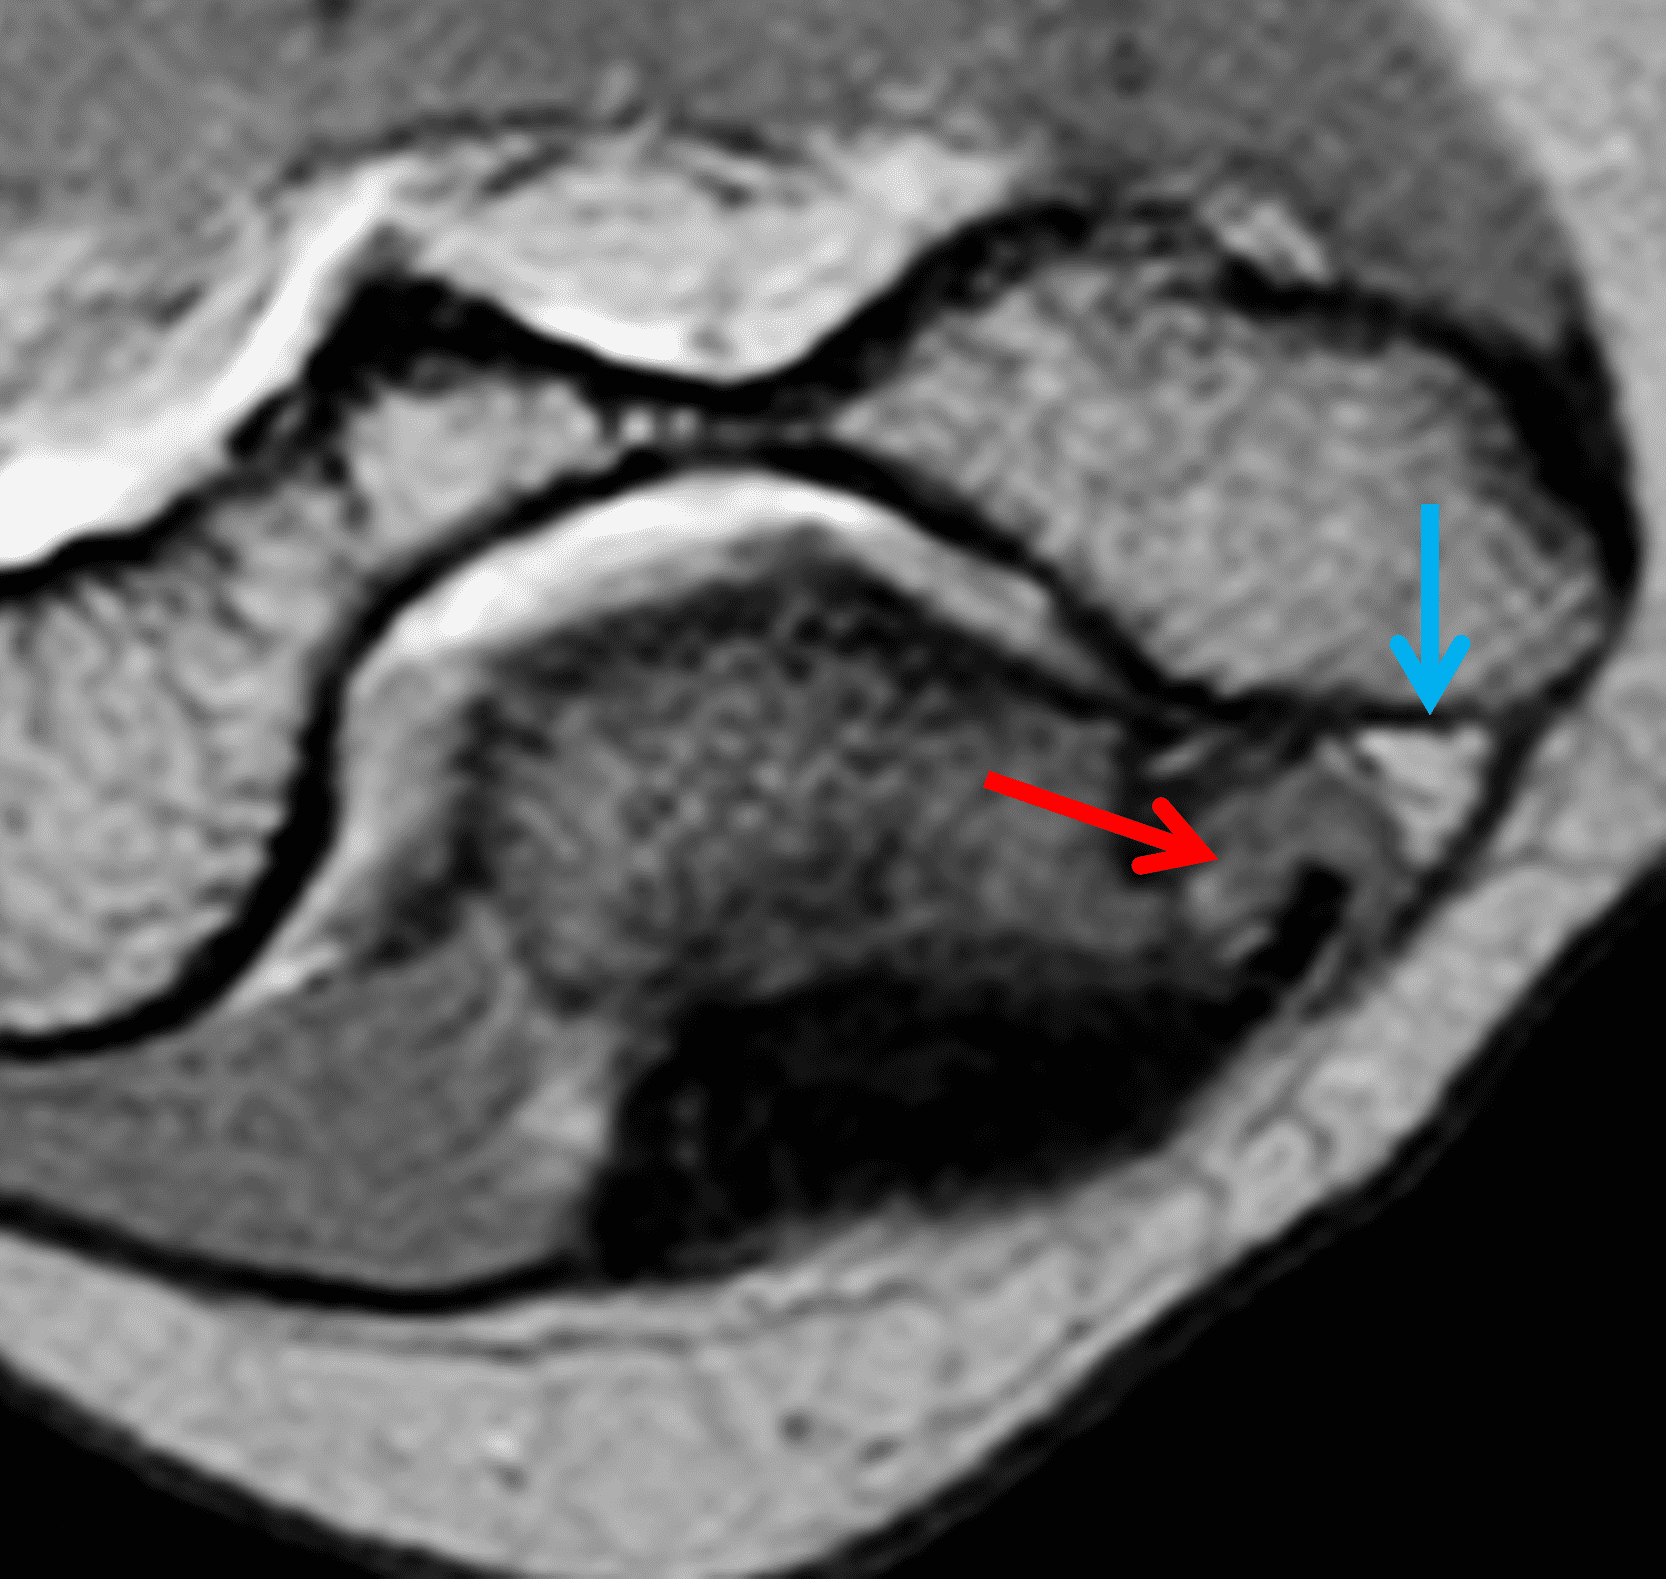

Figure 7: Absent cubital tunnel retinaculum. (7A) Drawing depicts absence of the retinaculum overlying the cubital tunnel contents. Compare with Figure 3B. (7B) Axial T1-weighted image with the elbow extended shows a normally-positioned ulnar nerve (arrow) with no defined retinaculum extending from the olecranon to the medial epicondyle. In the same patient with the elbow flexed, (7C) T1-weighted and (7D) fat-suppressed, fluid-sensitive images demonstrate dislocation of the ulnar nerve (arrows) relative to the medial epicondyle (ME).